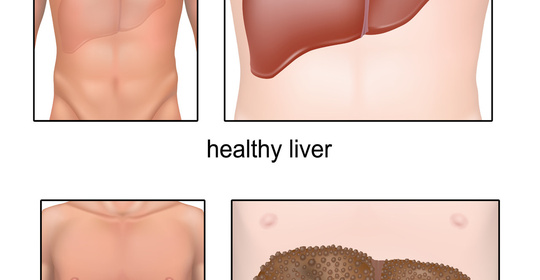

孕婦必讀:瞭解B型肝炎檢查和抗體對胎兒的影響